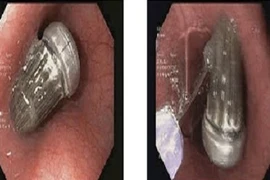

Trung tâm Y tế Nam Đàn (Nghệ An) vừa tiếp nhận và xử trí kịp thời cho một bệnh nhân 70 tuổi (trú xã Đại Huệ, Nghệ An) nuốt phải nắp chai khi uống nước.